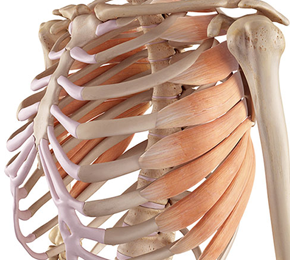

늑골이라고 명명되며 12쌍을 이루고 있는 갈비뼈는 내부의 심장, 폐, 간 등 주요 장기를 막아주는 역할은 물론 몸의 형태를 계속하고 정상적인 생활을 하는 데 있어 굉장히 귀중한 인체 부위에 부합됩니다.

갈비뼈 근처에 존재하는 많은 근육과 인대 부위에 경미하였거나 그렇지 아니하면 너무한 손상, 염증, 파열 등이 일어난 상태를 늑골 염좌, 갈비뼈 염좌라고 부릅니다 각별히인대의 손상 정도에 따라 과도한 멍, 붓기, 통증이 결성되며 완전한 파열이 발생되었을 때에는 작열감, 숨 쉴 때 불편감이 심할 수 있고요.

갈비뼈를 연결하는 늑간근의 근육 긴장이나 부상은 갈비뼈 오른쪽에 통증을 발생시킬 수 있다고 합니다. 이 통증은 날카롭거나 둔할 수 있기도하고 움직이거나 심호흡을 하다가 보면 안좋아질 수 있다고 합니다. 근육 긴장은 갑작스러운 뒤틀림이나 들어 올리기, 가슴 근육의 많은 사용 또는 부때맞은 들어 올리기 기술로 인해 발생할수 있습니다.